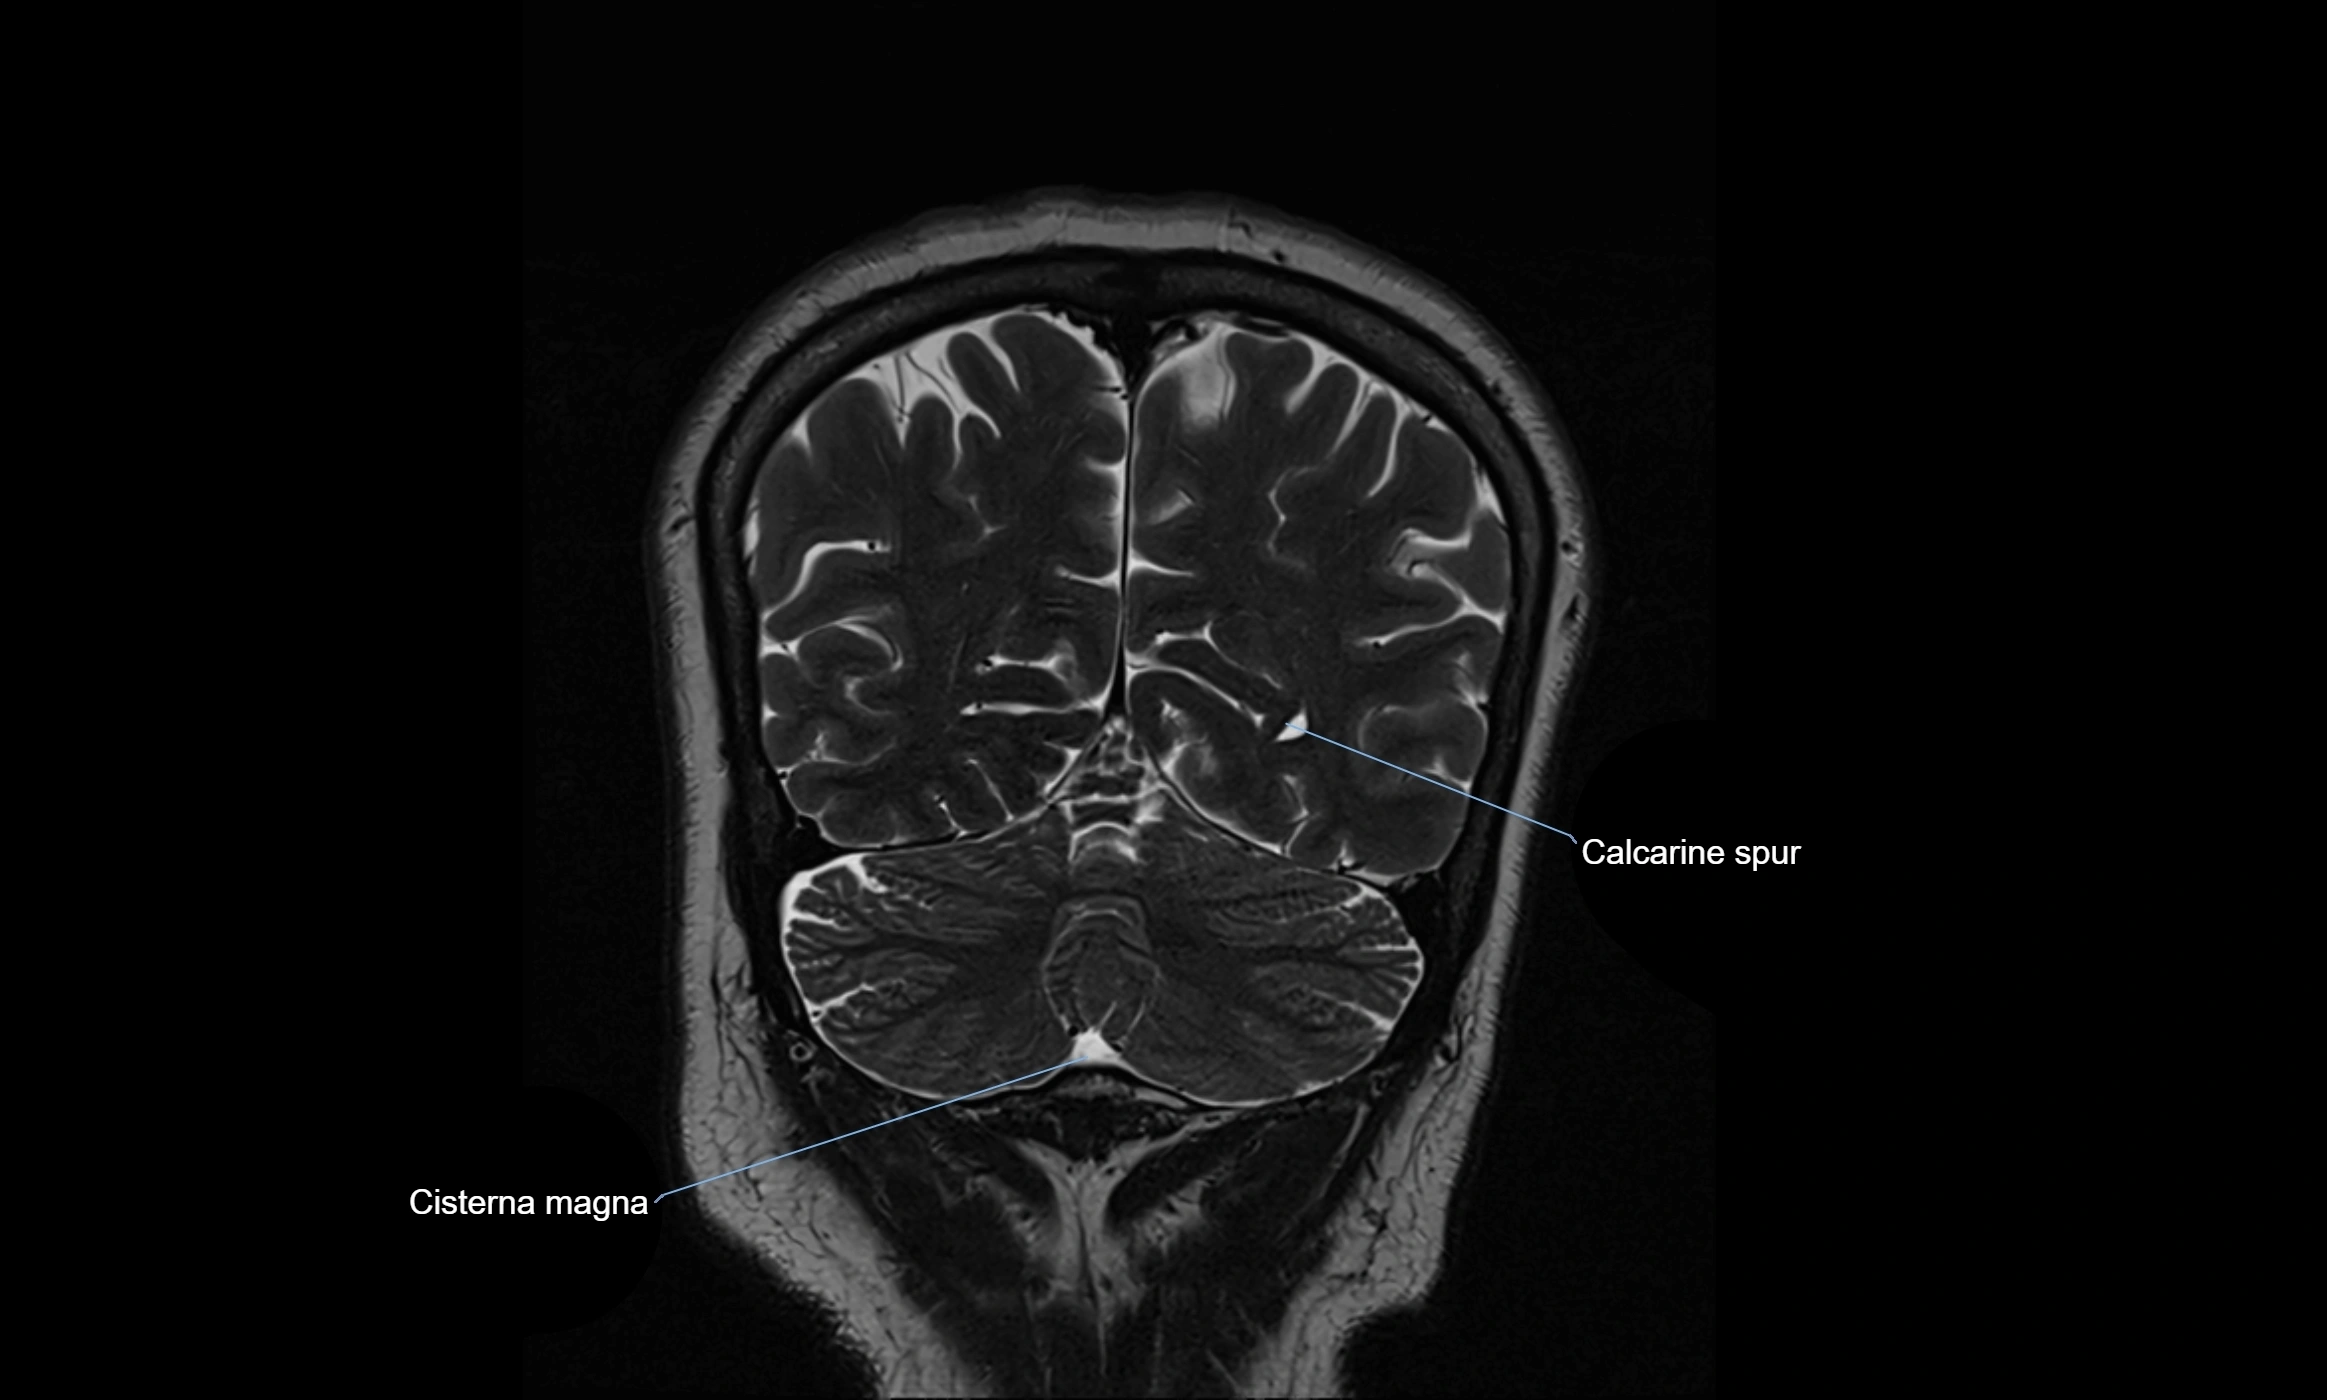

MRI images

image